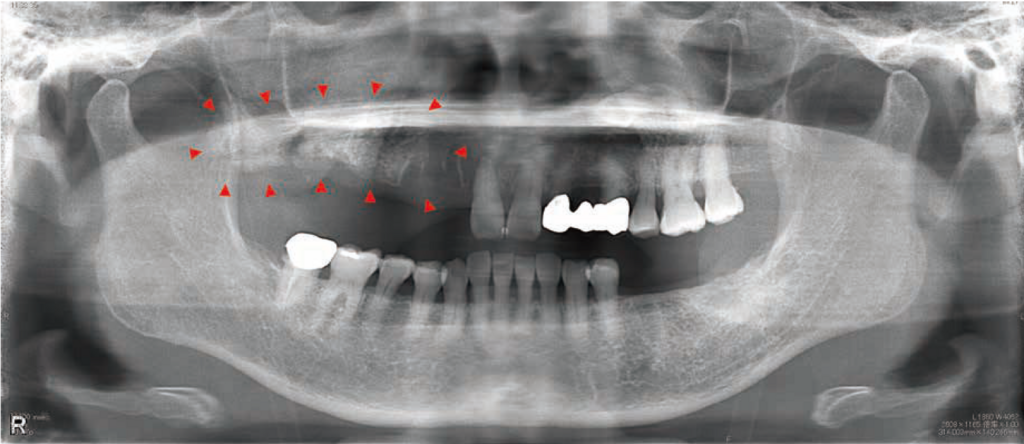

初診時:パノラマX線写真

上顎右側前歯部から臼歯部にかけての骨硬化像ならびに右側上顎洞に陰影を認めた。

初診4か月前と初診時:骨SPECT/CT画像の比較

原因となった右上6部から近心に向かって、右上2にかけて骨の腐骨化が進行してきている。

顎骨の粗造部分に一致してRI薬剤の集積が抜けており、周囲の骨に集積している像が見られた。